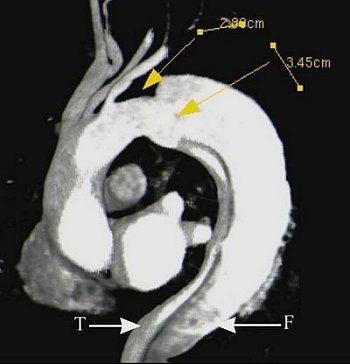

The series of images illustrate the typical manifestations of aortic dissection, including Stanford A (top image, both VR; second image, axial MPR) and Stanford B (third image, arterial phase VR, venous phase VR; fourth image, MIP and VR; fifth image, axial MPR). T = true lumen. F = false lumen. Black arrowhead = entry site. All images courtesy of Qi Liu, Ph.D.